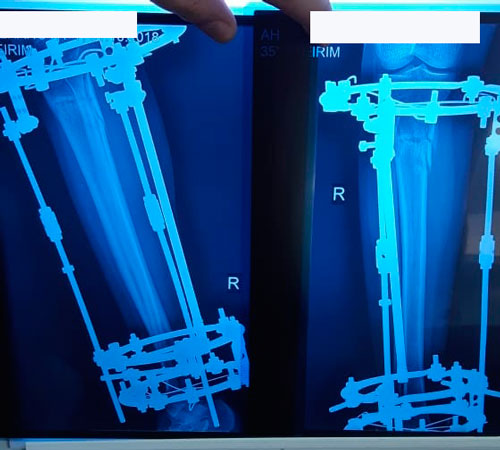

60 дней после операции

Дата операции 04.07.2018г.

Дата снятия аппаратов 16.10.2018г.

Срок сращения - 102 дня.